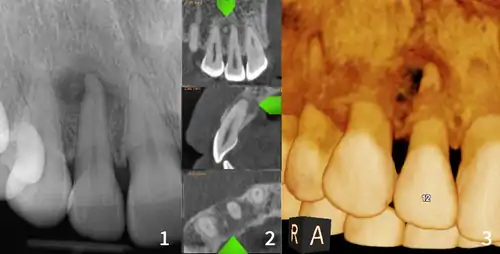

| Florid osseous dysplasia of the mandible | |

| Diagnostic method | X-ray, CBCT scan, vitality testing of teeth |

Diagnosis is important so that the treating doctor does not confuse it for another periapical disease such as rarefying osteitis or condensing osteitis. Incorrect diagnosis could lead to unnecessary root canal treatments. It can be diagnosed by radiographic appearance. Confirming the tooth is vital, as is noting the demographic (African American females).[1][2][3]